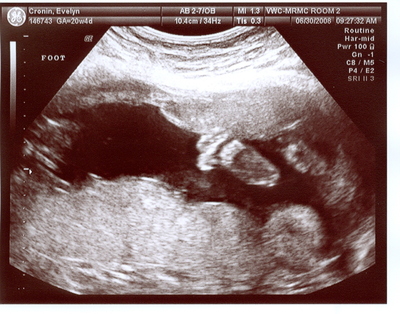

See the feet? One is clear and the other is to the right.